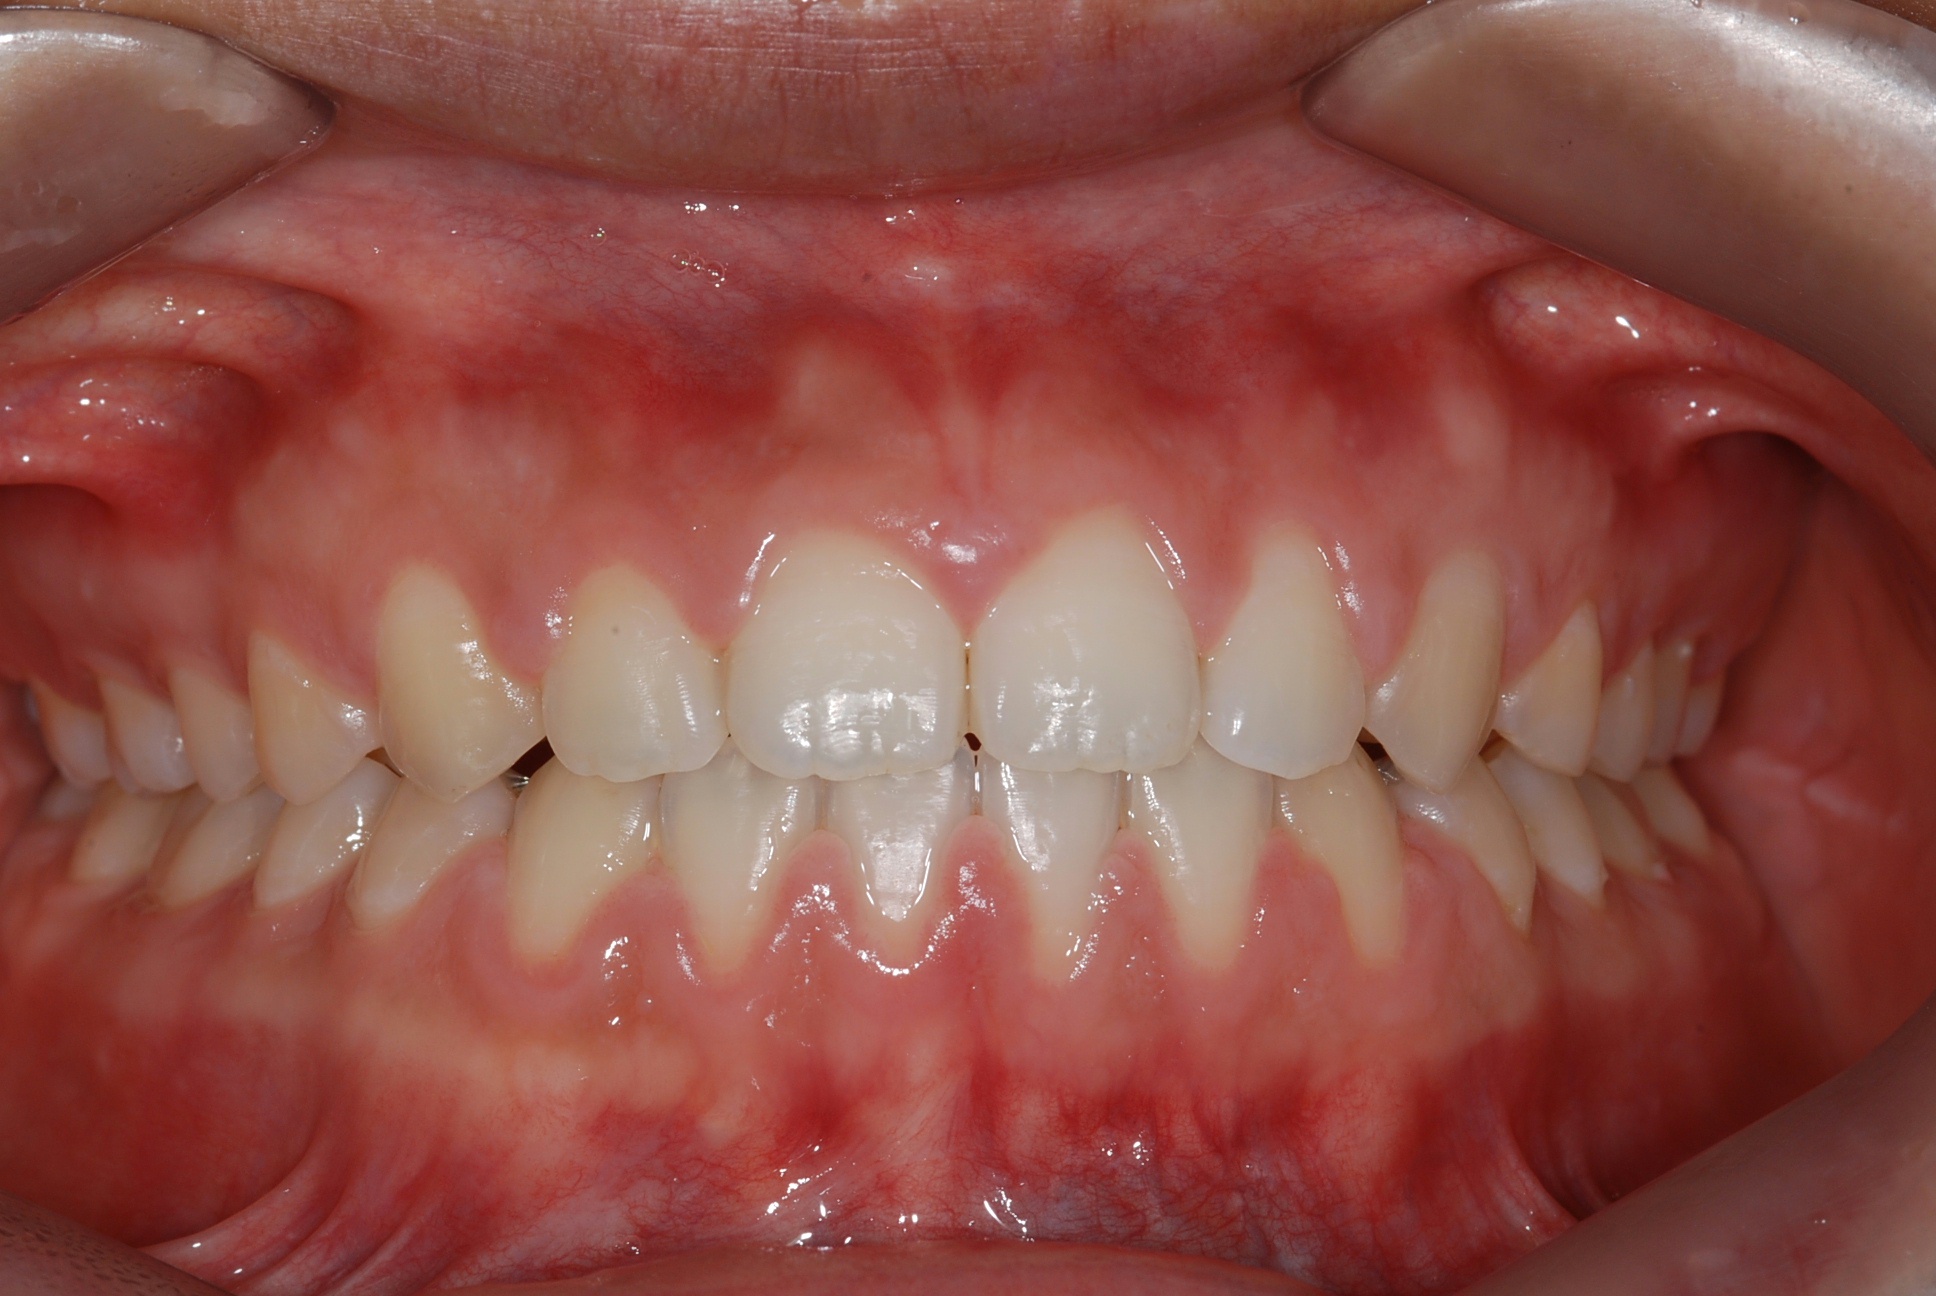

치료 후 사진입니다.